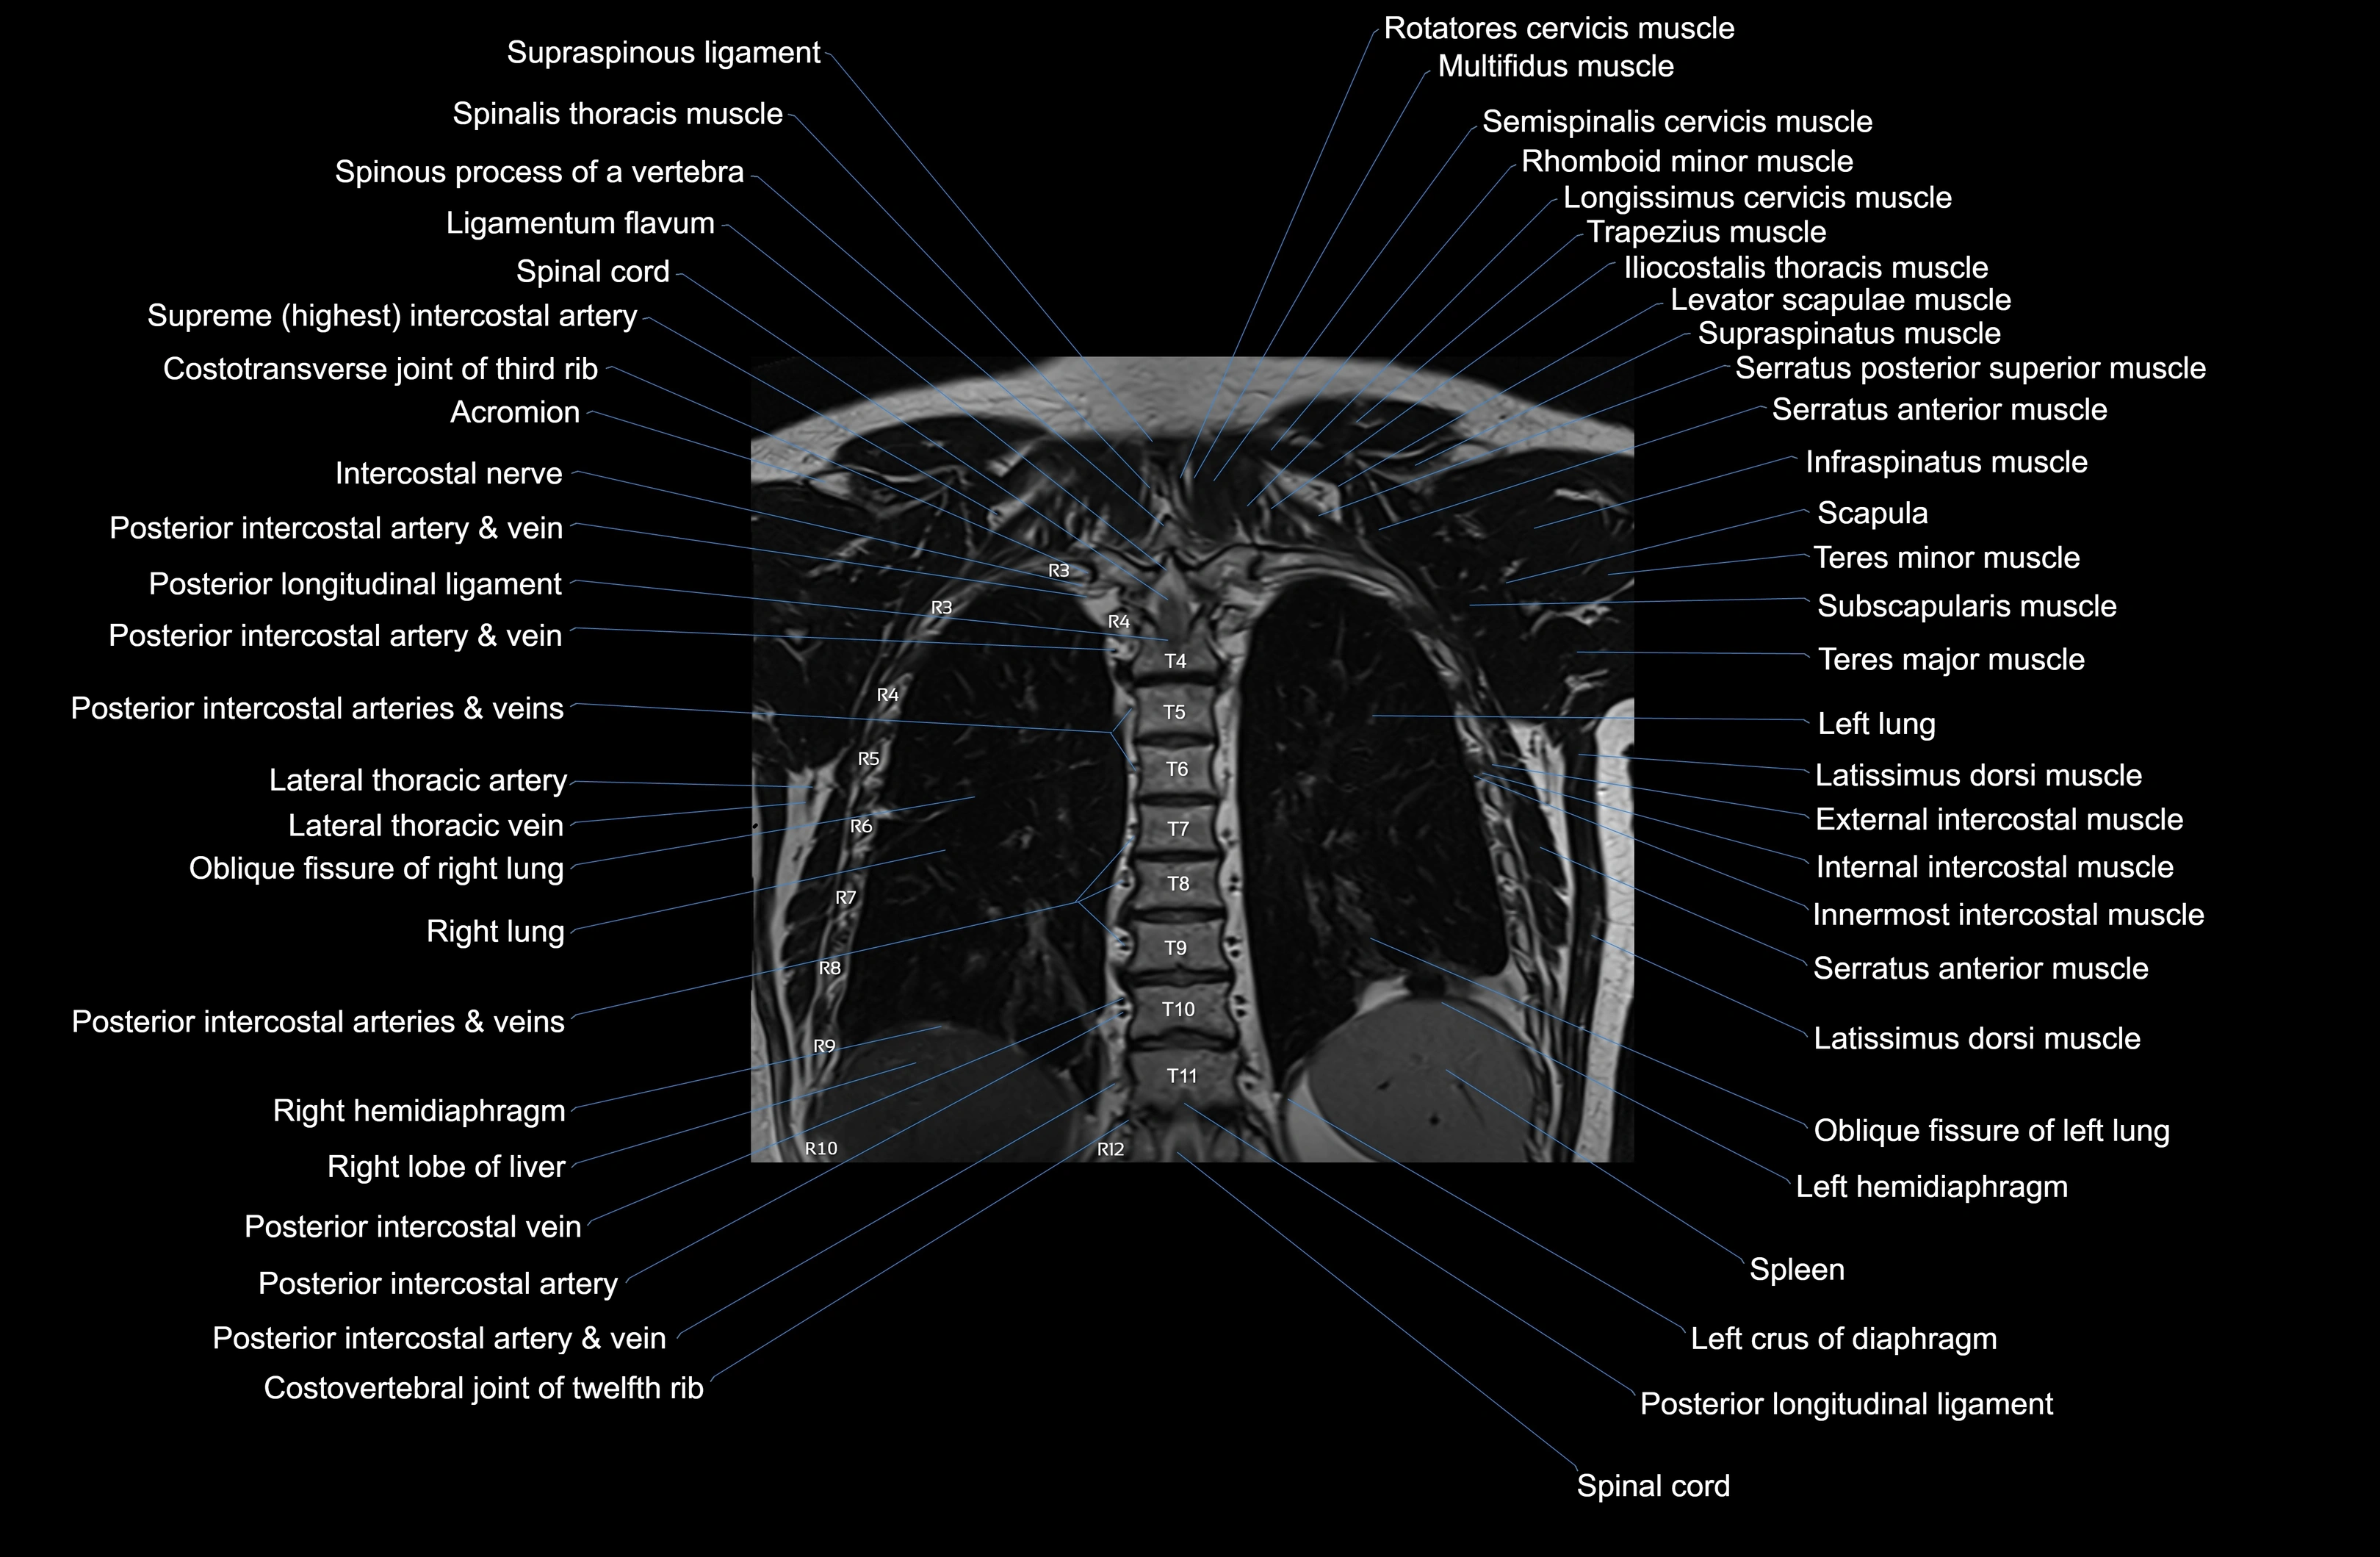

- Posterior intercostal arteries

- Posterior intercostal veins

- Serratus anterior muscle

- Serratus posterior inferior muscle

- Serratus posterior superior muscle

- Supraspinatus muscle

- Trapezius muscle